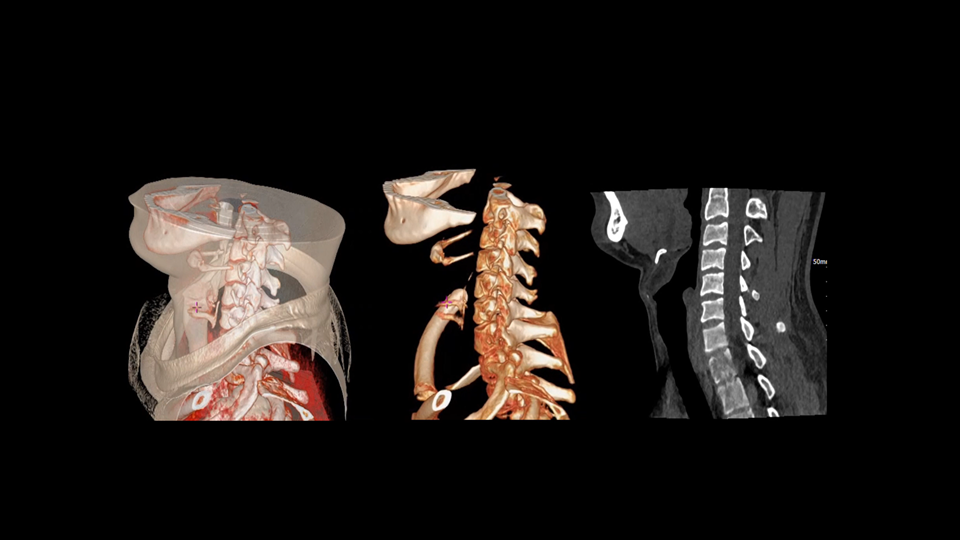

全身各部位动态CT成像

uCT SiriuX® 以16cm超宽Z轴覆盖,使超高时间分辨率应用于完整器官成像。无论是心脏搏动还是关节运动,整个目标区域可在同一瞬时被完整、清晰地捕捉,彻底消除时序误差,实现从“局部瞬间”到“全器官瞬时”的成像跨越。

全器官同步

uCT SiriuX® 以全新双宽体系统架构,同步实现超高时间分辨率与宽体容积覆盖兼得,全面释放性能潜能,敏锐捕捉人体生理运动全景,带来动态影像新视角。

双宽体“零”噪声时空探测器,Z 方向覆盖达16 cm,单圈即可完整扫描头颅、心脏等关键器官,结合超高时间分辨率,可实现真正意义上的全身各部位高清动态成像,让每一次扫描都更高效、更精准。